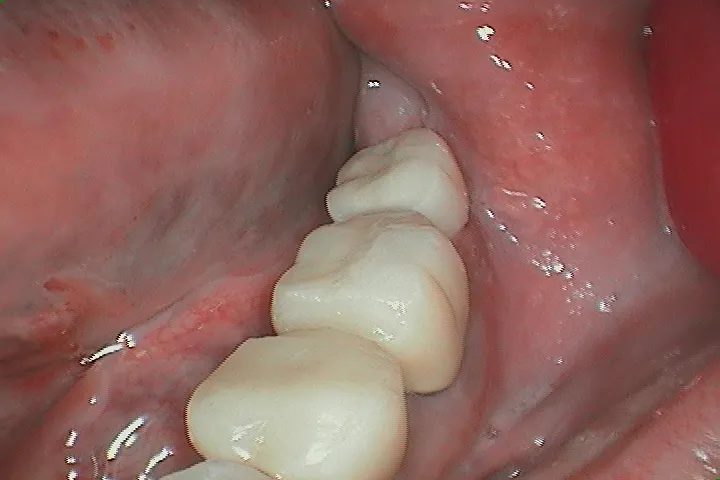

欠けている歯のためのブリッジ治療

前

![橋の前に隙間のある歯]()

後

![ブリッジ配置後の歯]()